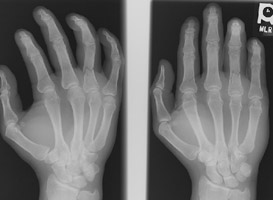

- Click on the image for a larger versionBPA and oblique radiographs of the hand. The also show the fracture of the fourth proximal phalanx.